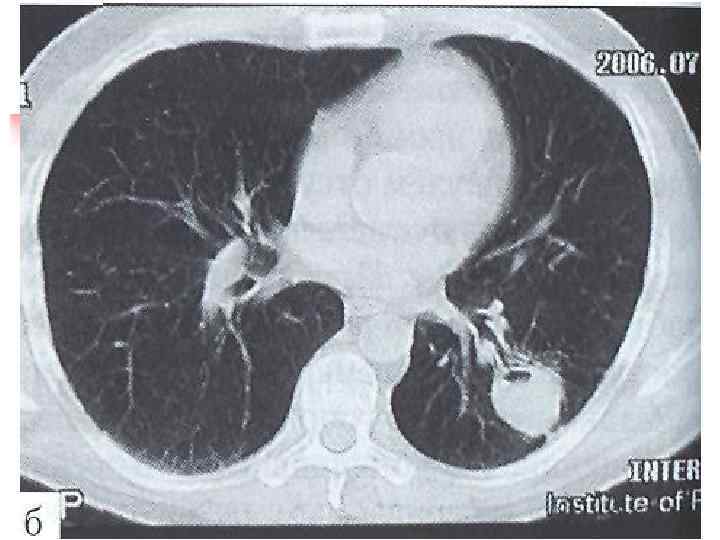

Очаговая реакция n n Изменение рентгенологической или ультразвуковой характеристики очага Появление бактериовыделения (промывные воды бронха)